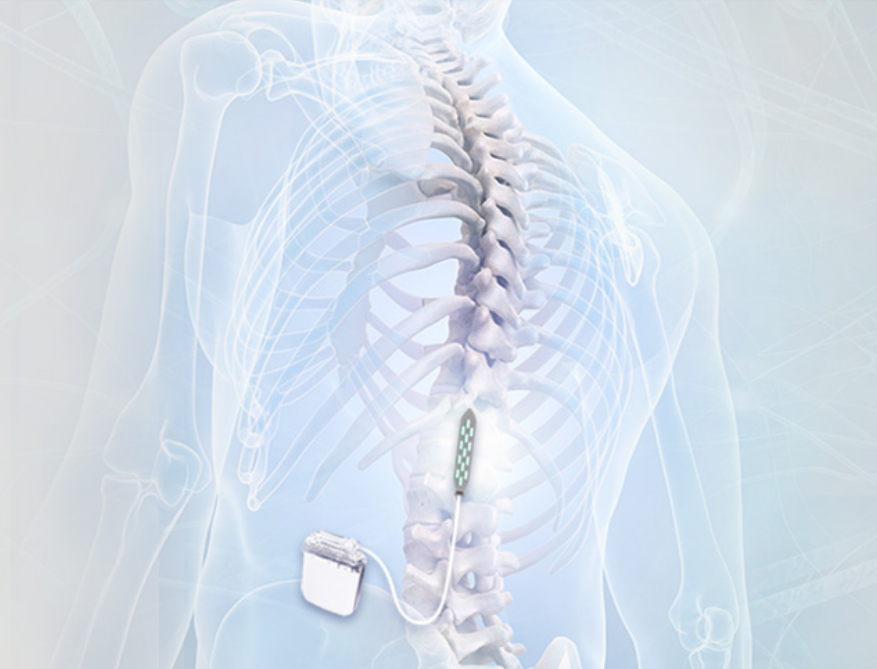

Epidural electrical stimulation was introduced in the 1970s to help alleviate abnormal muscle tightness due to prolonged muscle contraction in Multiple Sclerosis (Click here to read more about this). We spoke about the epidural space above in our description of the spinal cord. Epidural electrical stimulation involves a stimulating electrode, which has an array for different stimulating points:

A stimulating electrode. Source: Epiduralstimulationnow

This stimulating electrode is surgically placed in the epidural space so that the stimulating pads of the electrode are facing the spinal cord:

Source: Epiduralstimulationnow

The electrode is then connected to a stimulator which can be programmed to provide very specific patterns of stimulation to the area of the spinal cord where the electrode has been placed.

Source: Researchgate